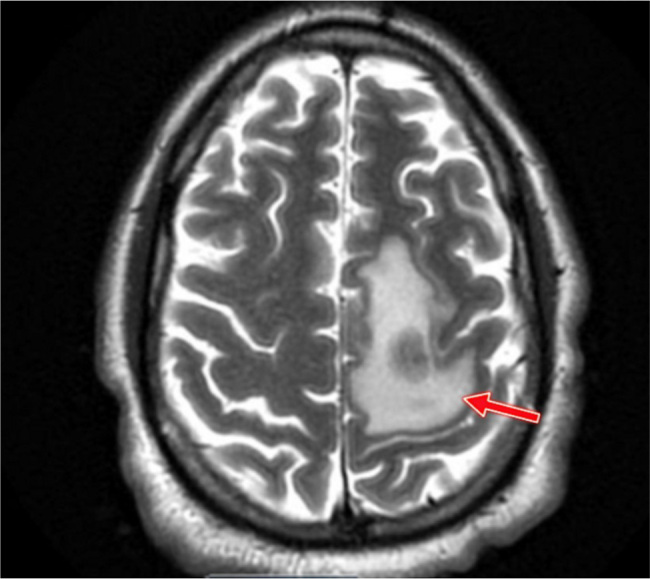

Case presentation: We describe a newly diagnosed 43-year-old HIV-positive male with concurrent Hodgkin lymphoma who presented with progressive neurological decline and a ring-enhancing brain lesion. While histopathological analysis of the brain biopsy demonstrated features of HIV-associated leukoencephalopathy, PCR testing paradoxically identified Aspergillus fumigatus; however, histopathological examination failed to demonstrate definitive fungal elements. Despite negative cerebrospinal fluid galactomannan and β-D-glucan assays, empiric voriconazole therapy was initiated in accordance with current treatment guidelines. Over the ensuing month, the patient returned with worsening neurologic status, radiographic lesion progression, and ultimately developed Torsades de Pointes, and multiorgan failure, resulting in death.